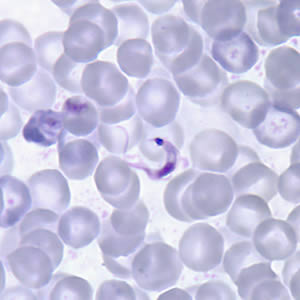

P. vivax

P. ovale

P. malariae

P. falciparium

Babesia